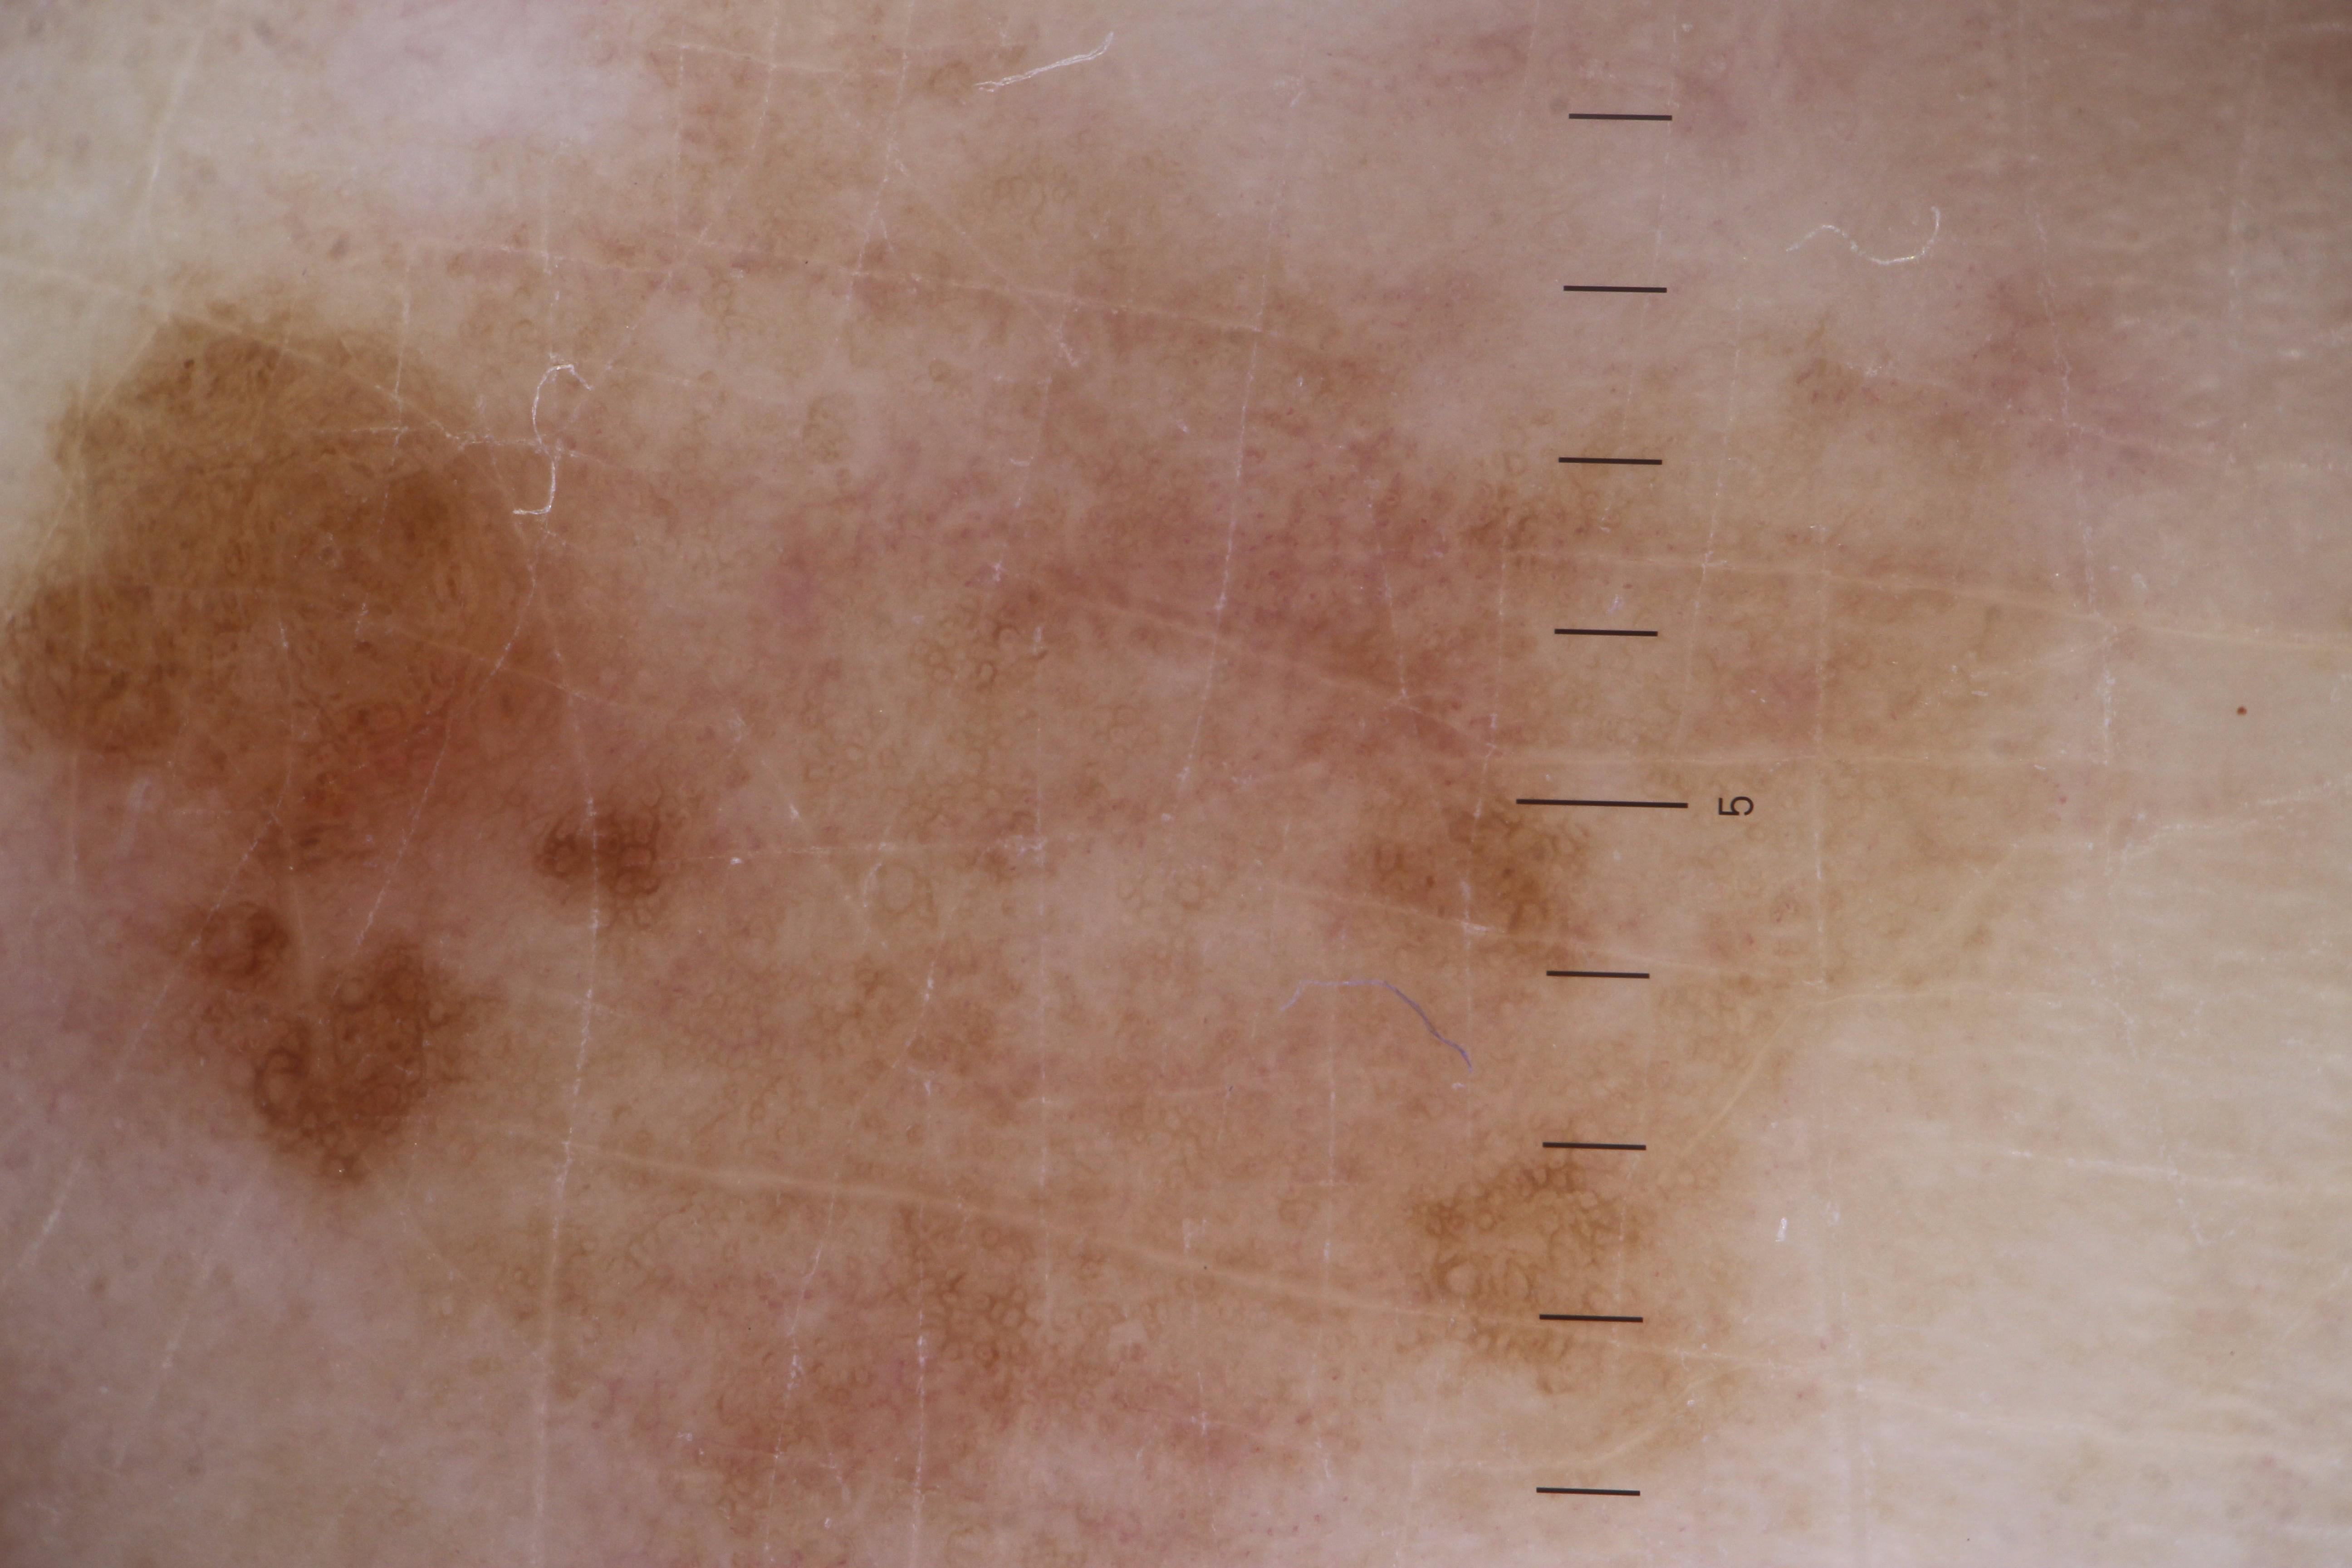

ISIC_5852089

Clinical

| Field | Value |

|---|---|

| acquisition_day | 1173 |

| age_approx | 55 |

| anatom_site_1 | Lower extremity |

| anatom_site_2 | Foot |

| anatom_site_special | acral NOS |

| concomitant_biopsy | False |

| diagnosis_1 | Benign |

| diagnosis_confirm_type | serial imaging showing no change |

| fitzpatrick_skin_type | II |

| image_type | dermoscopic |

| lesion_id | IL_2074851 |

| patient_id | IP_9124285 |

| sex | male |